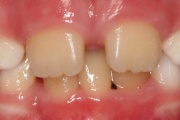

Puudub ülemine tsentraalne intsisiiv, kuid külgmised lõikehambad on juba lõikunud.

Turritavad ülemised lõikehambad.